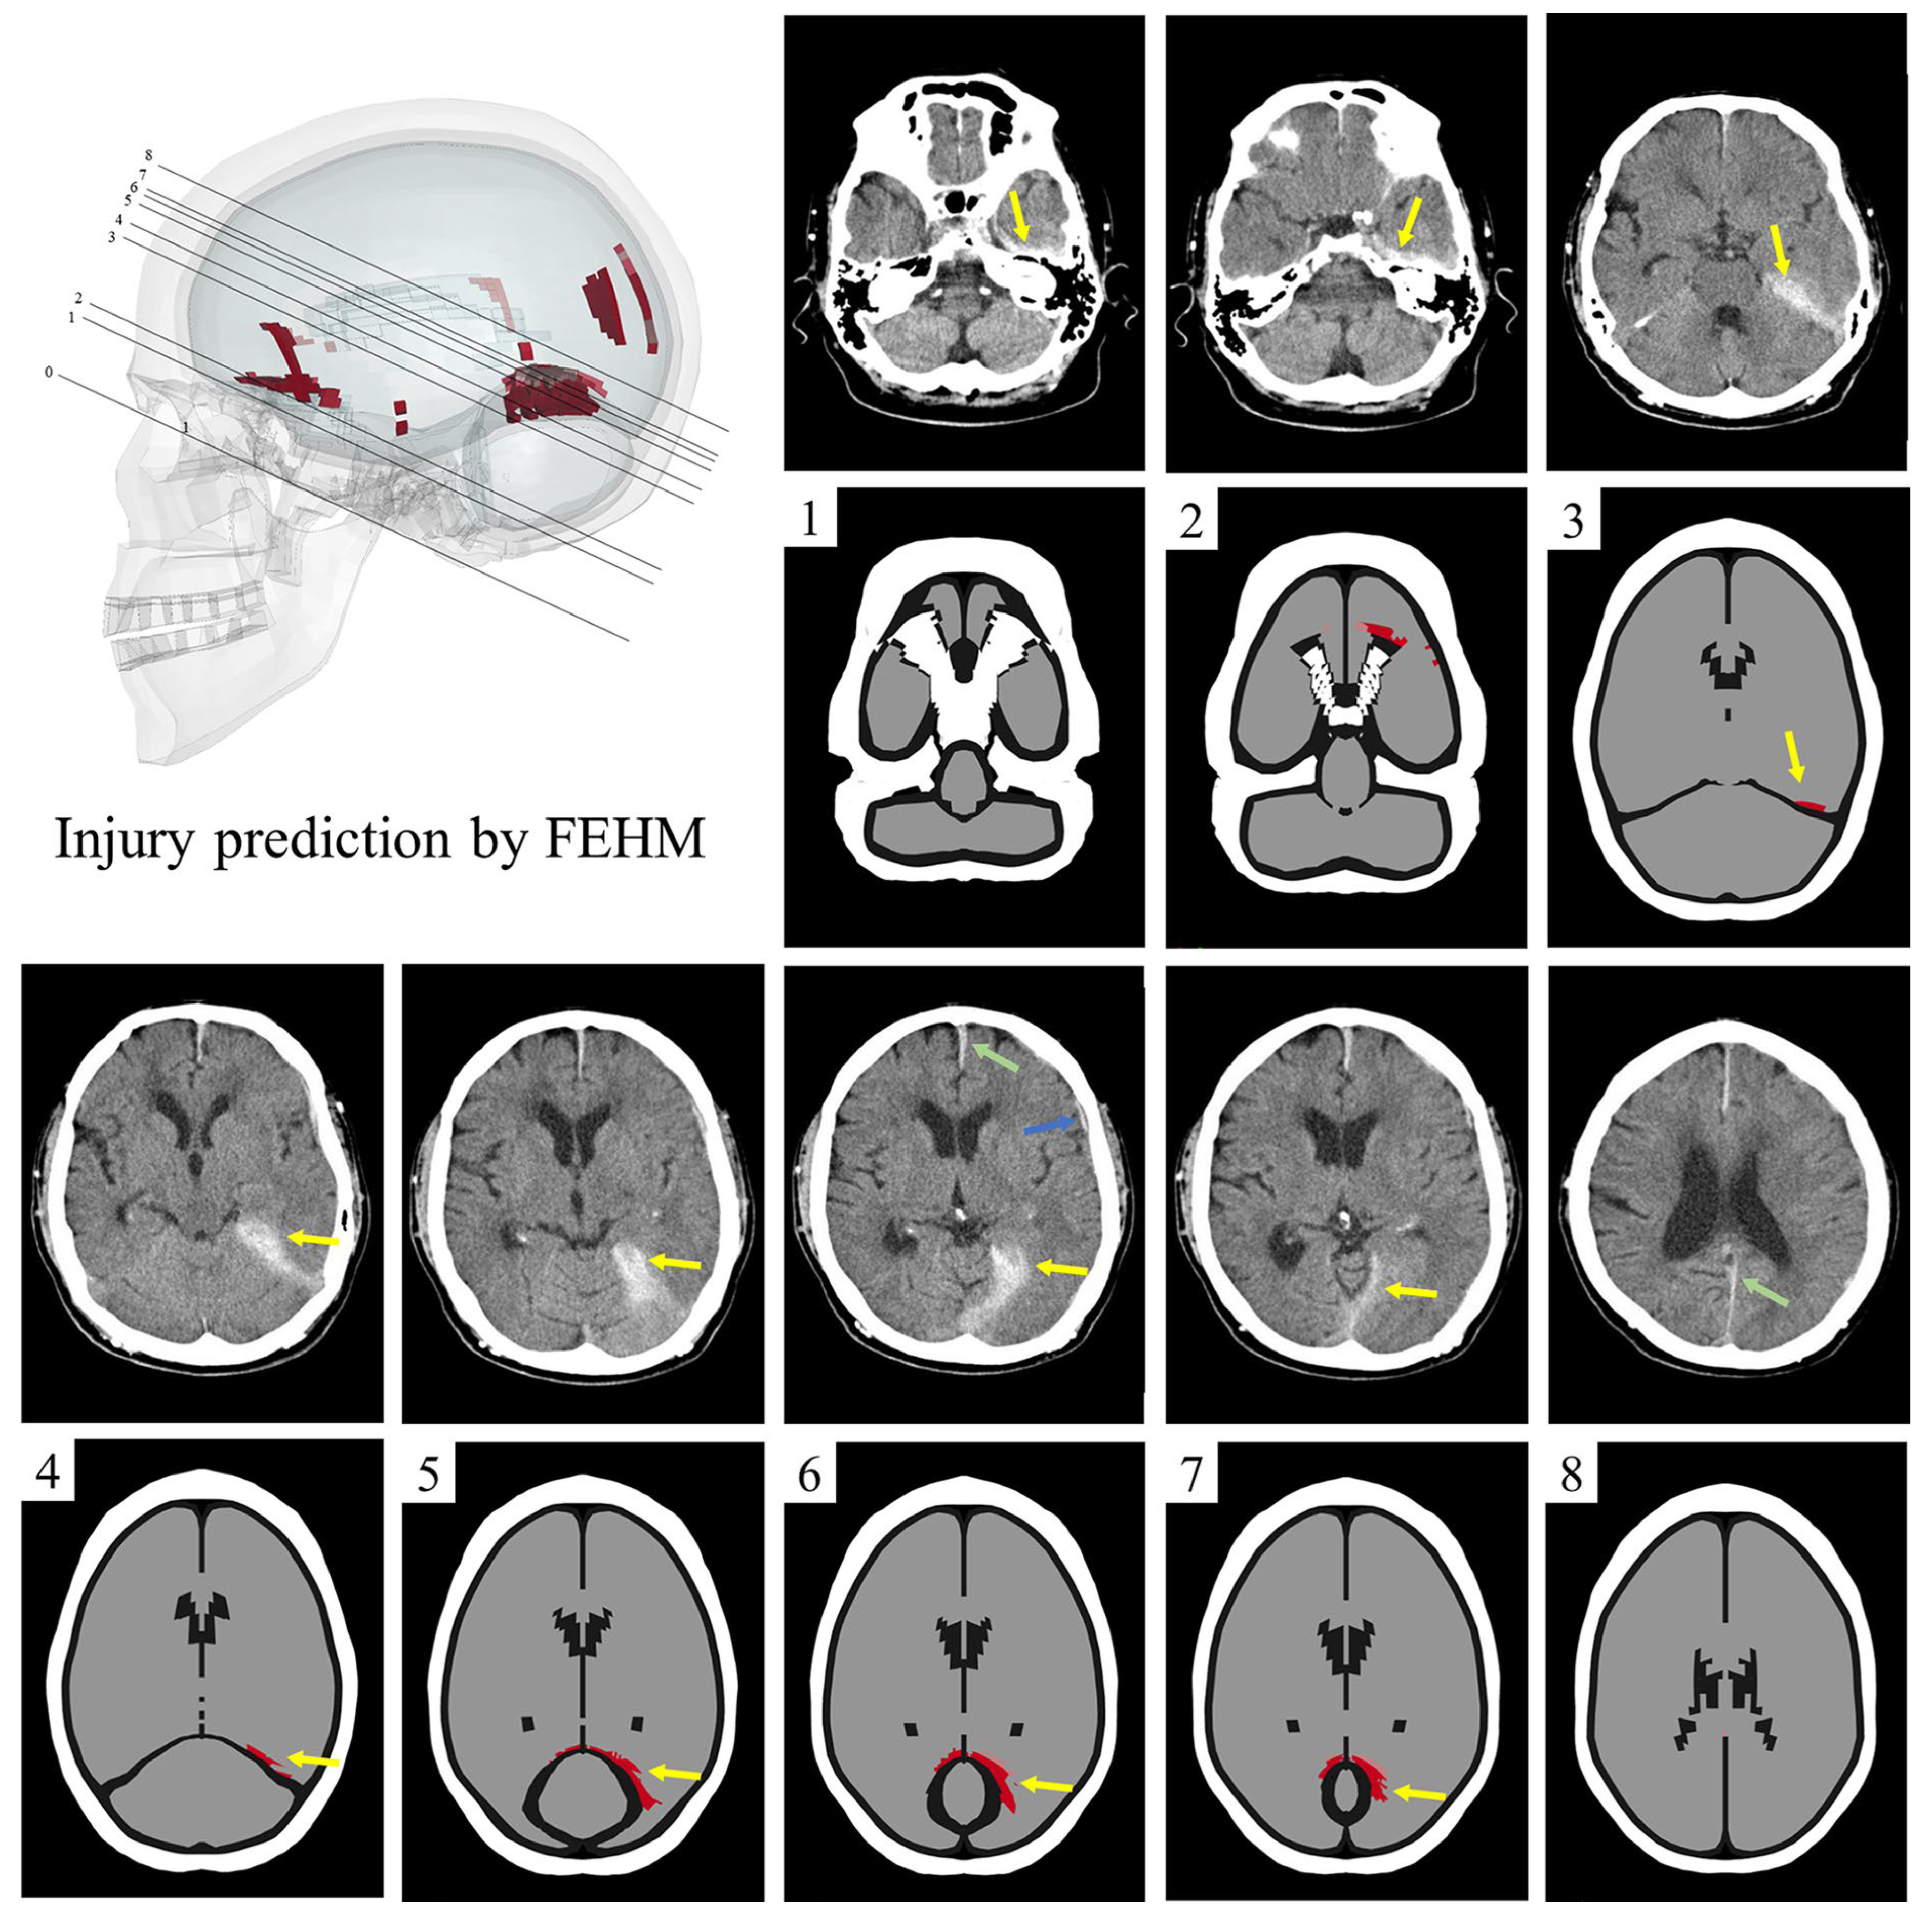

3.2. Injured Areas in FEHM and CT Images